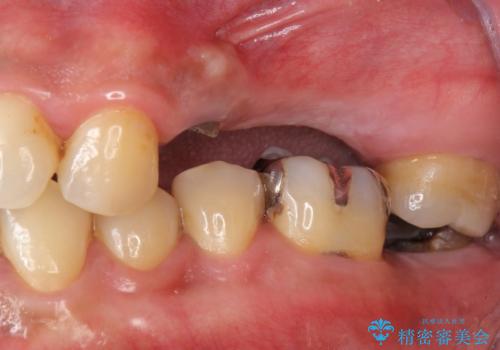

- 長期間放置してしまった虫歯の治療を希望され来院されました。

・重度虫歯による残根状態・欠損歯→インプラント補綴

・対合歯の欠損による歯の挺出→マイクロインプラントを用いた小矯正を行うことで咬合平面を是正

今回、左下6は頬側歯頚部に虫歯があり圧下を行ったことからクラウンにより補綴を行いました。